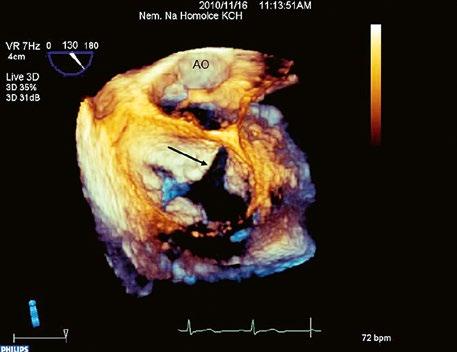

Obr. 45.13 Amplatzerův okluder uzavírající defekt septa síní II (3DE TEE)

z K uzávěru jsou indikovány hemodynamicky významné defekty i bez symptomů, jeli plicní cévní rezistence (PVR) nižší než 5 WU(7, 14) (Tab. 45.2).

Video 45.9 3DE TEE

Amplatzerův okluder uzavírající defekt septa síní II